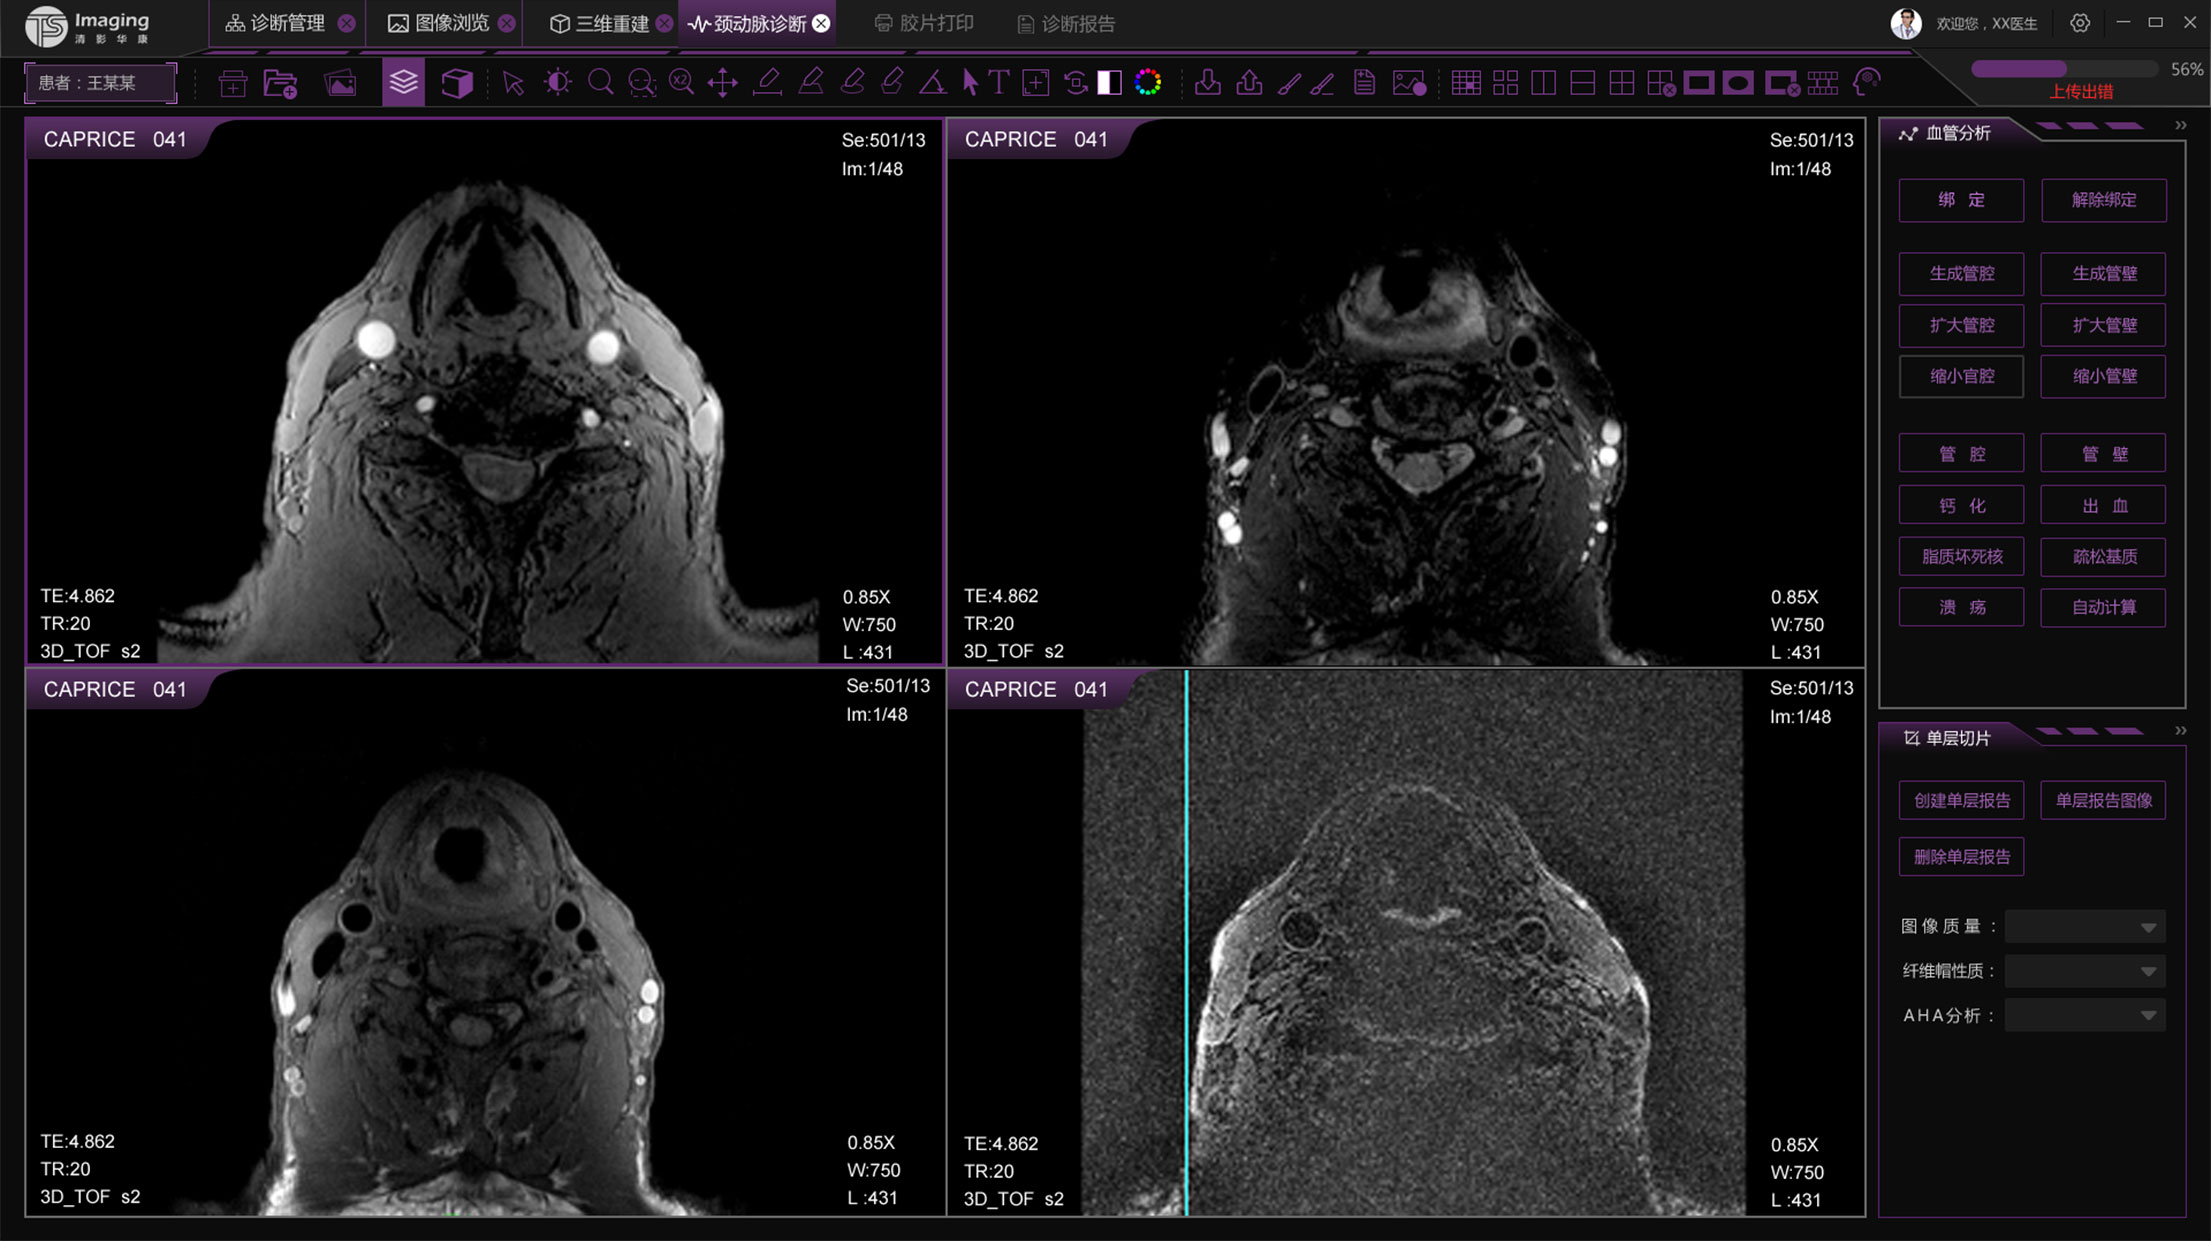

頸動脈診斷頁面

頸動脈診斷頁面整體布局和三維重建比較相似,最大的區別是右側的操作區域,血管分析都為按鍵操作,通過間隔的大小分成三部分。單層切片除了按鍵還有下拉菜單的操作。

頸動脈診斷原型